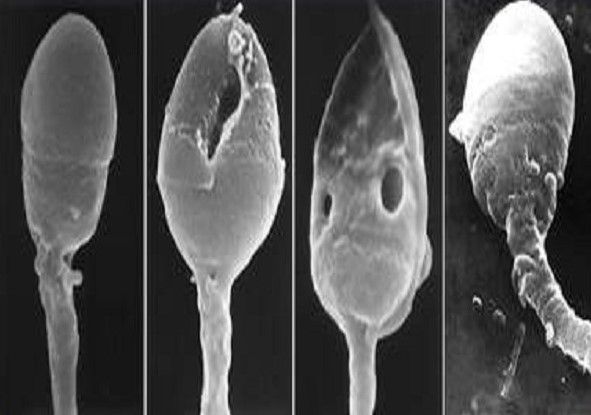

De nouvelles données scientifiques montrent qu’il existe des caractéristiques spécifiques à la morphologie du sperme, comme certaines «bulles» qui sont appelées vacuoles, dont la présence est une indication de pathologie de l’ADN du sperme. De très petite taille, ces vacuoles ne sont pas visibles avec les méthodes actuelles, raison pour laquelle la technologie IMSI a été développée.

Grâce à l’utilisation de lentilles spécifiques, les microscopes pour l’IMSI permettent de grossir les spermatozoïdes jusqu’à 10 000 fois, ce qui permet d’observer l’intérieur de la tête, rendant visibles beaucoup plus de caractéristiques.